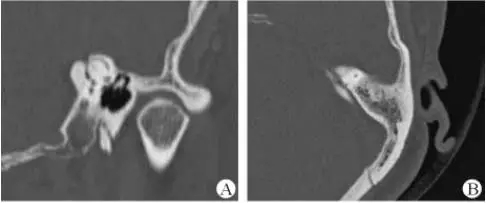

医生若怀疑此病将会安排内耳CT扫描。在大多数案例中,一旦此病被耳鼻喉科医生或其它听力健康专家确诊,则可实行手术治疗。外科手术风险包含听力损失以及神经损伤;重建及复原需内耳的治疗以及大脑的重塑。

先天性胆脂瘤,长在鼓膜后并在出生时已存在。医学专家认为这种情况是由皮肤细胞在错误的地方生长造成。获得性胆脂瘤,常发生于成人,这些人患有慢性或反复性耳部感染。

幸运地是,医生在耳部检查的时候能看到珍珠白样的聚集物。大部分的胆脂瘤能通过外科手术移除。若不处理,胆脂瘤将长大并漫延侵润,造成内耳结构的永久性破坏导致眩晕以及平衡问题或面部神经以及肌肉的破坏,造成麻痹。